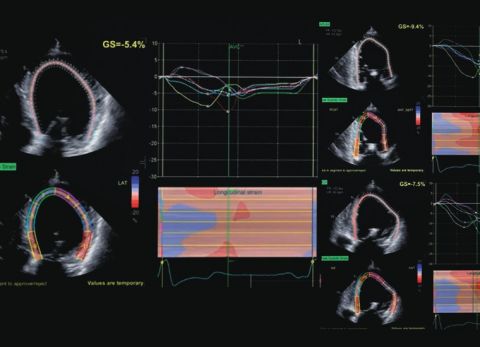

prof. dr hab. n. med. Jarosław KasprzakDane kliniczne:Pacjentka z niewydolnością sercaRozpoznanie główne:Kardiomiopatia przerostowa z zawężaniem drogi odpływu lewej komoryPoruszane zagadnie...